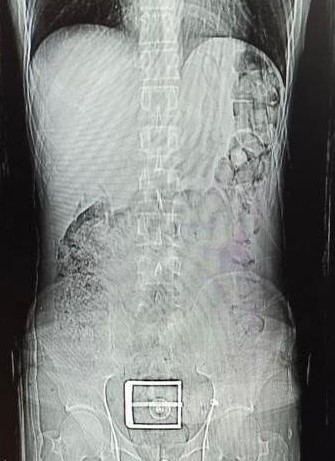

Edinilen bilgiye göre, Narkotik Suçlarla Mücadele ekiplerinin madde ticareti ve nakline yönelik yapılan çalışmalar sonucunda durumundan şüphelenilerek yakalanan ve uyuşturucu maddeleri yutarak nakletmeye çalışan İran uyruklu F.S. (30) yapılan iç beden muayeneleri sonucunda mide ve bağırsak kısmında 78 kapsül halinde 603,35 gr Afyon Sakızı ve 17 kapsül halinde 111,35 gr Metamfetamin maddeleri ele geçirildi.